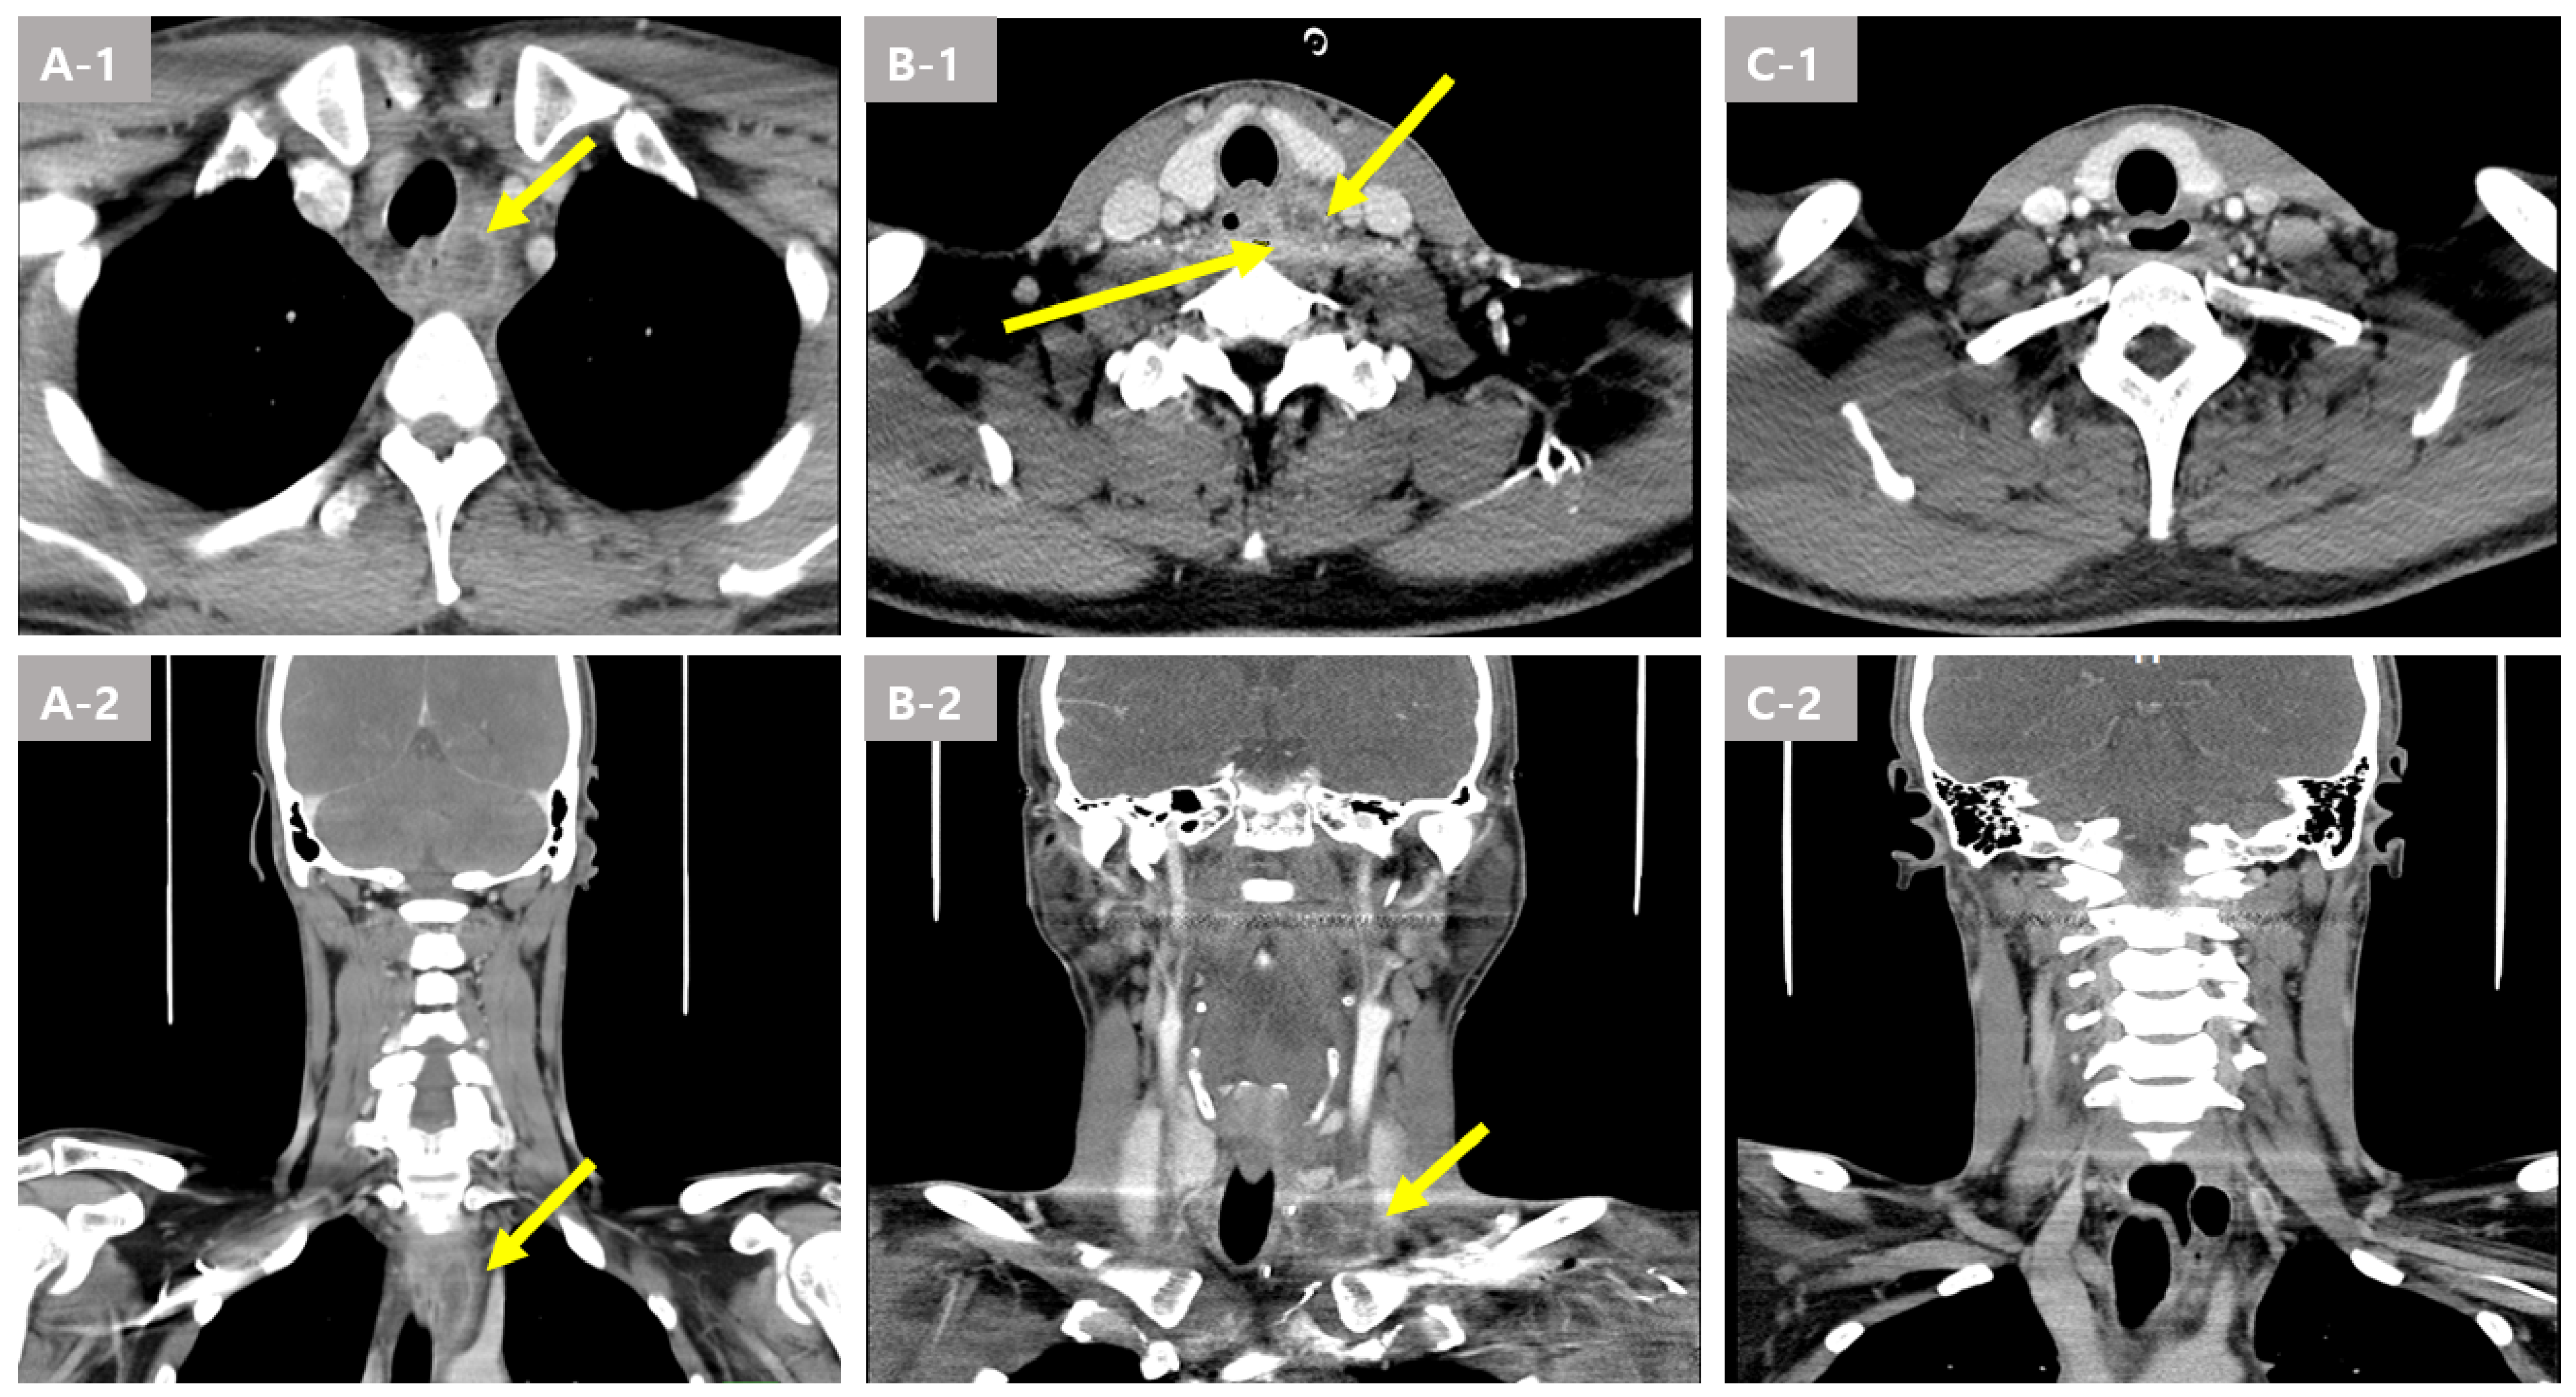

Laboratory tests showed leukocytosis (WBC 17,350 μL, normal range: 4500–11,000 μL) and elevated C-reactive protein (CRP, 120.7 mg/L, normal range: 0–5 mg/L). A neck computed tomography (CT) scan showed complicated esophagitis with a 1.2 cm para esophageal abscess formation (Figure 1(A-1,A-2)).

An additional neck CT scan was performed the next day. Although the patient underwent a surgical operation and broad-spectrum antibiotic therapy, the neck CT scan showed aggravated paratracheal and paraesophageal areas multiloculated with abscess cavities (Figure 1(B-1,B-2)).

Two weeks later, a neck CT scan showed a marked decrease in the size of the preexisting multiloculated abscess cavities (Figure 1(C-1,C-2)). A follow up upper endoscopy found a mucosal defect; however, the abscess was improved. In addition, esophagography was performed prior to feeding, and there was no leakage. As a result, endoscopic intraluminal drainage was successfully performed, and the patient was discharged without complications. The patient visited the outpatient clinic 4 weeks after discharge, and there were no symptoms suggestive of esophageal stricture, such as difficulty swallowing. Follow up endoscopy performed thereafter also confirmed healed mucosa without stricture.

Figure 1. Image findings of the esophageal abscess due to a fish bone foreign body in Case 1. (A-1,A-2) A complicated esophagitis with paraesophageal abscess formation (arrow) in the esophagus was revealed by a computer tomography (CT) scan at the local hospital. (B-1,B-2) paratracheal and paraesophageal areas; multiloculated abscess cavities (arrow) in the esophagus were revealed by the CT scan at 2 days. (C-1,C-2) Markedly decreased size of the preexisting multiloculated abscess cavities in the left visceral space and left sided mediastinum by the CT scan.